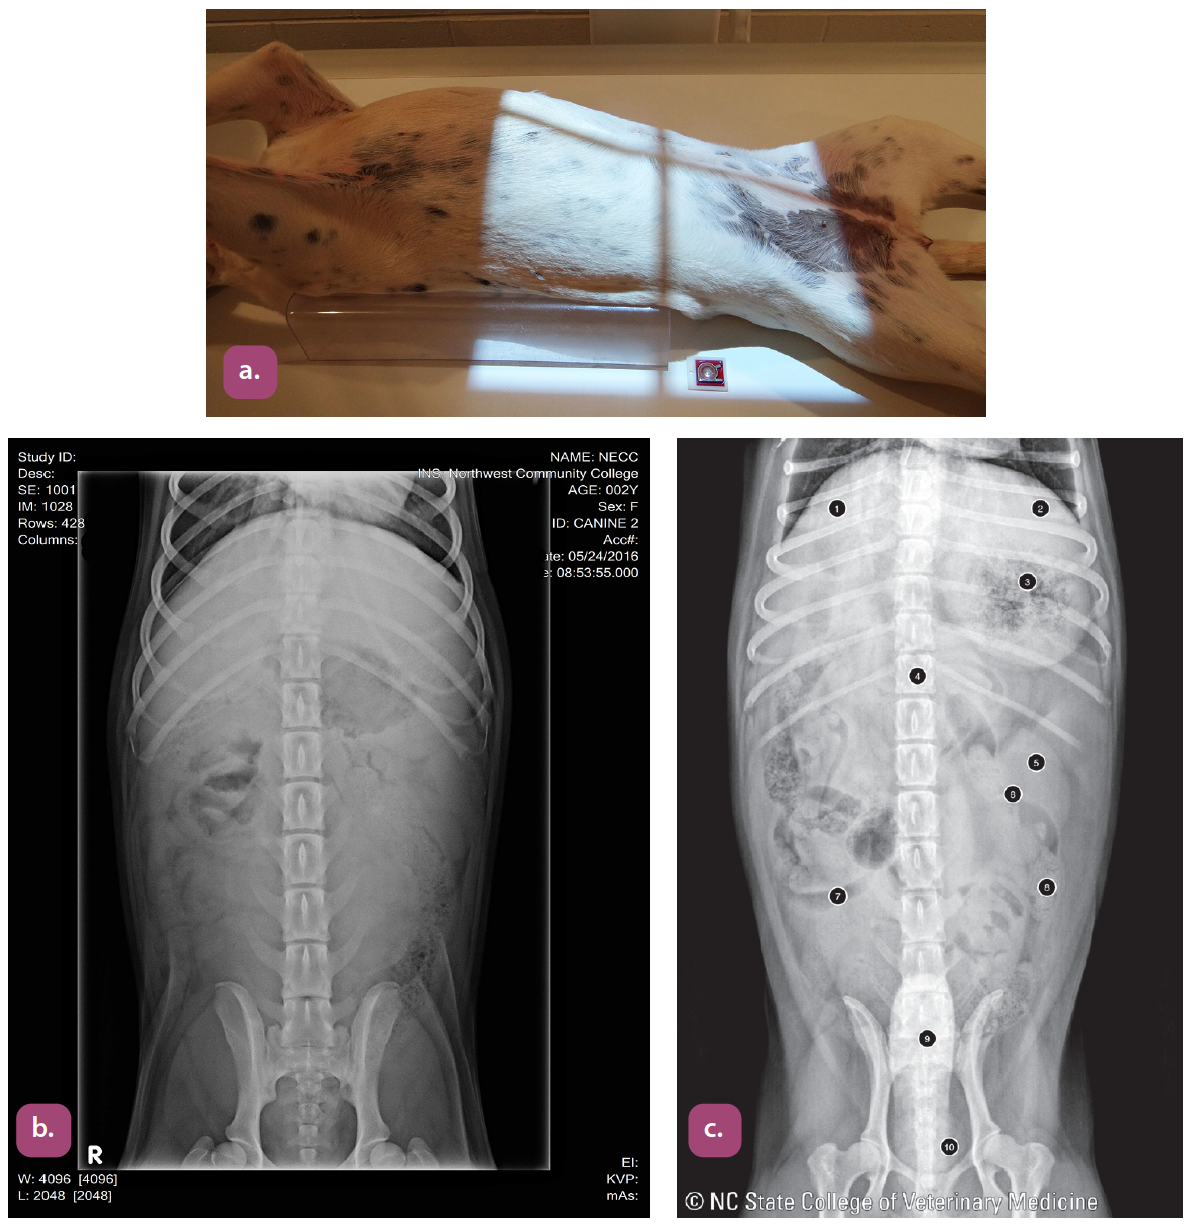

lateral projection of the abdomen

ventrodorsal projection of the abdomen

ventrodorsal projection of abdomen with the horizontal beam (lateral decubitus)

modified lateral projection